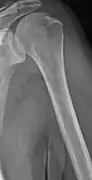

Medical imaging

The diagnostic examination of a person with suspected multiple myeloma typically includes a skeletal survey. This is a series of X-rays of the skull, axial skeleton, and proximal long bones. Myeloma activity sometimes appears as "lytic lesions" (with local disappearance of normal bone due to resorption) or as "punched-out lesions" on the skull X-ray ("raindrop skull"). Lesions may also be sclerotic, which is seen as radiodense.[70] Overall, the radiodensity of myeloma is between −30 and 120 Hounsfield units (HU).[71] Magnetic resonance imaging is more sensitive than simple X-rays in the detection of lytic lesions, and may supersede a skeletal survey, especially when vertebral disease is suspected. Occasionally, a CT scan is performed to measure the size of soft-tissue plasmacytomas. Nuclear Medicine Bone scans are typically not of any additional value in the workup of people with myeloma (no new bone formation; lytic lesions not well visualized on nuclear bone scan).